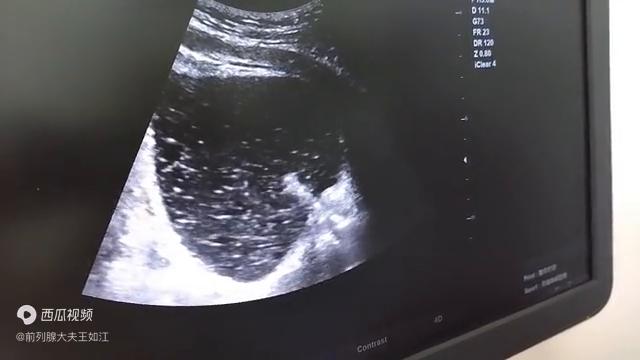

今天根据b超图像来让大家看一看,给大家讲一讲什么是尿道疏通扩张术。尿道扩张疏通术是积善堂,巧妙地利用导尿管和导尿管头上的水囊,巧妙地利用医疗器械,来对尿道里面的钙化灶,或者是对包绕卡压。

尿道内口的钙化灶,进行疏通和扩张的一种简便,但效果立竿见影的疗法。大家可以看图,一般做尿道疏通是选择在做钙化消融术至少在一周以上。它的前提是钙化灶必须首先被消融变得松软,这是它一个基础条件,变得松软。有很多钙化灶就最后分泌到了包绕尿道的叫黏膜下腺体。

刚才这个图大家看都很清楚,大量的白色絮状物,斑片状的物质,而且清晰地看到了尿道内口被水囊扩开的一个过程。这个尿道扩张疏通术,它只是用的最简单的一些普通导尿管,巧妙的用了它水囊的这种柔软的,无创的扩张作用。起到了这个效果。